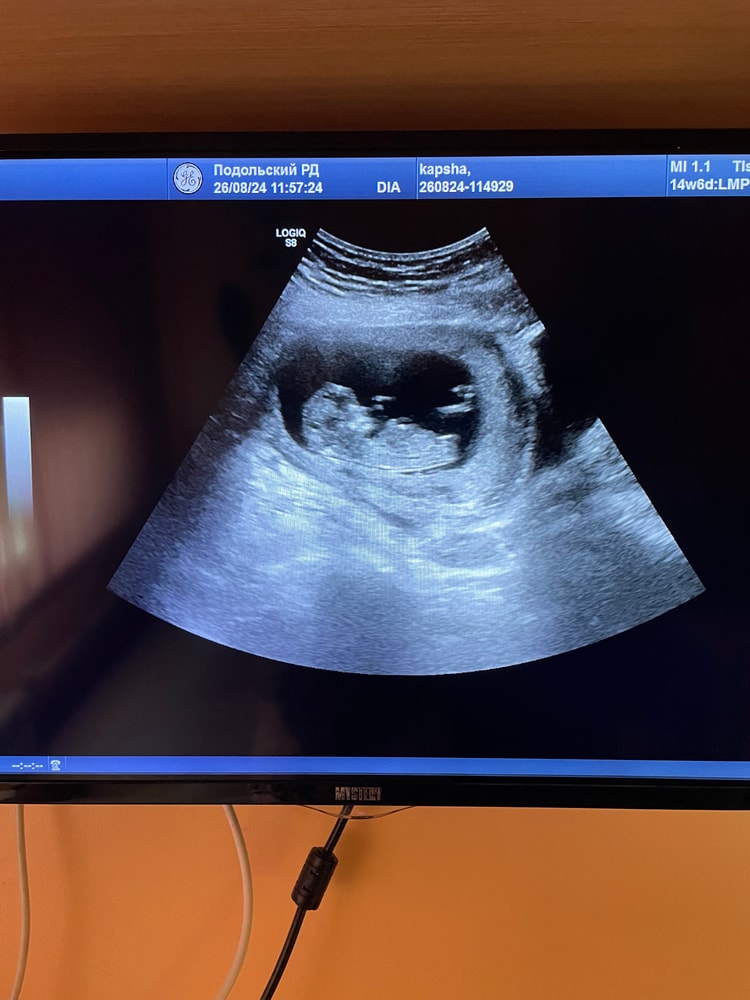

Кто в животике живёт (гадаем по фото УЗИ; результаты НИПТ или УЗИ)Девочки, есть кто разбирается? По данному фото можно предположить пол моего малыша?🙈🥹

Девочка, у мальчиков он под другим углом)